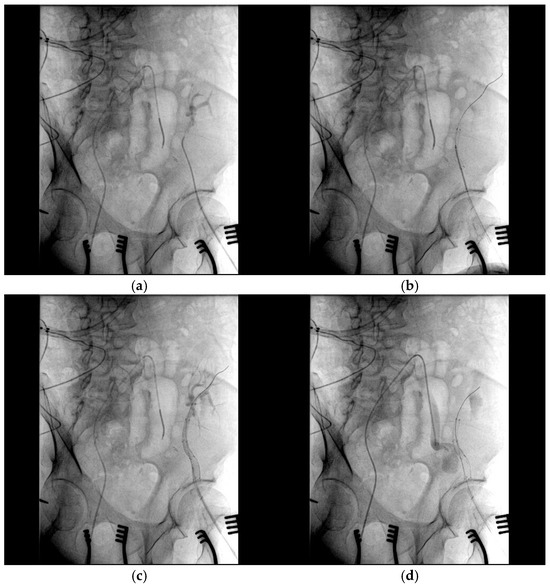

2. Case Report